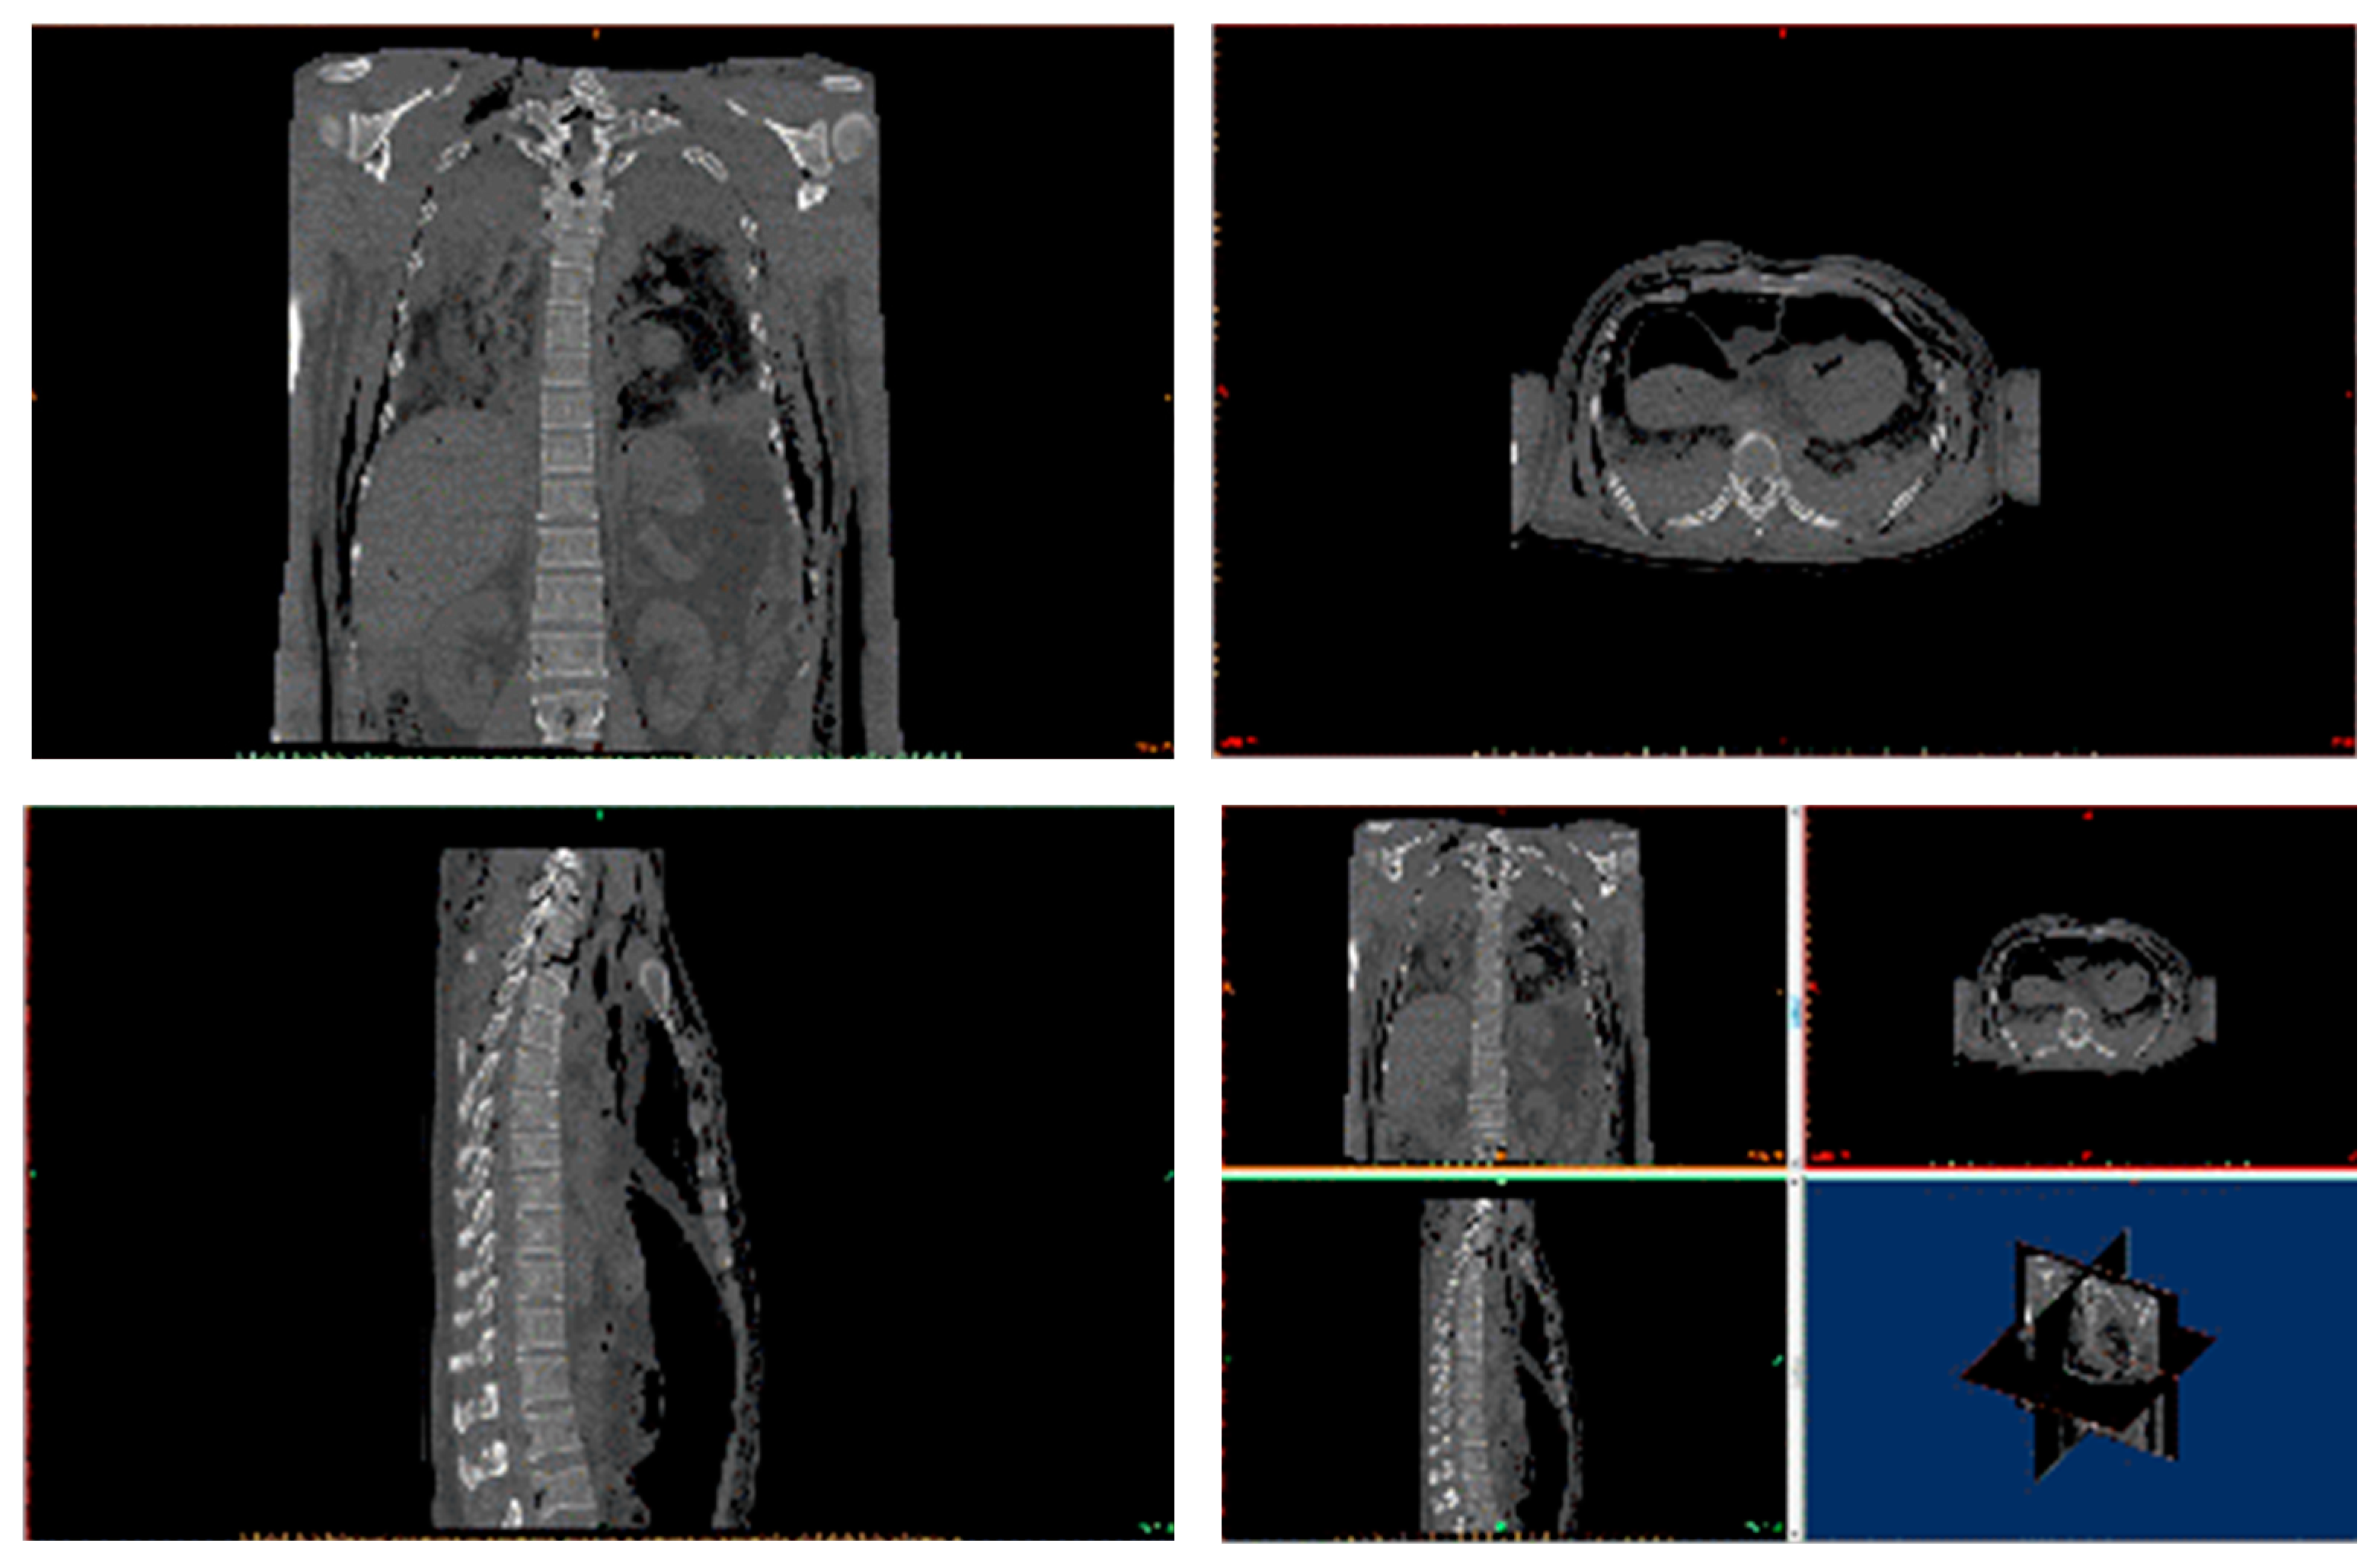

2. Background of Damaged Human Body

3. Reconstruction of the Damaged Human Model